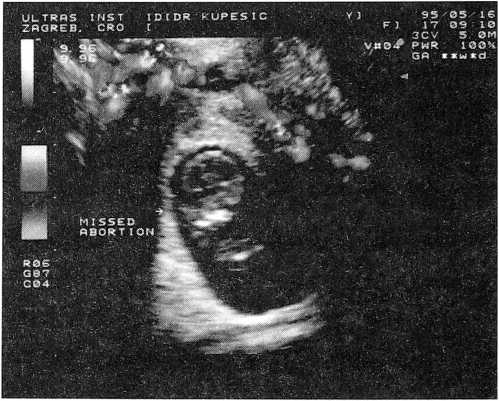

Диагноз неполного выкидыша характеризуется наличием плода с отсутствием сердечной деятельности [58] (рис. 2).

Рис. 2. Неразвиваюшаяся беременность; отсутствует циркуляция крови у плода

Это состояние определяется как тип спонтанного аборта, при котором после гибели плода не произошла спонтанная экспульсия из матки плодного яйца [11]. Ультразвуковая картина при этой патологии зависит от времени, прошедшего с момента гибели эмбриона и прекращения у него кровообращения. Так, при недавней гибели эмбриона форма плодного яйца и визуализация эмбриона, как правило, не изменены. В дальнейшем наблюдаются изменения формы, размеров плодного яйца, морфологии эмбриона, а также изменения ткани трофобласта. Последняя становится негомогенной, возможно наличие кальцифицированных участков, определяются также гематомы, участки отслойки плодных оболочек. При допплерометрии основным параметром неразвивающейся беременности является отсутствие сердечной деятельности и цветового сигнала кровотока после 6 недели гестации [63].